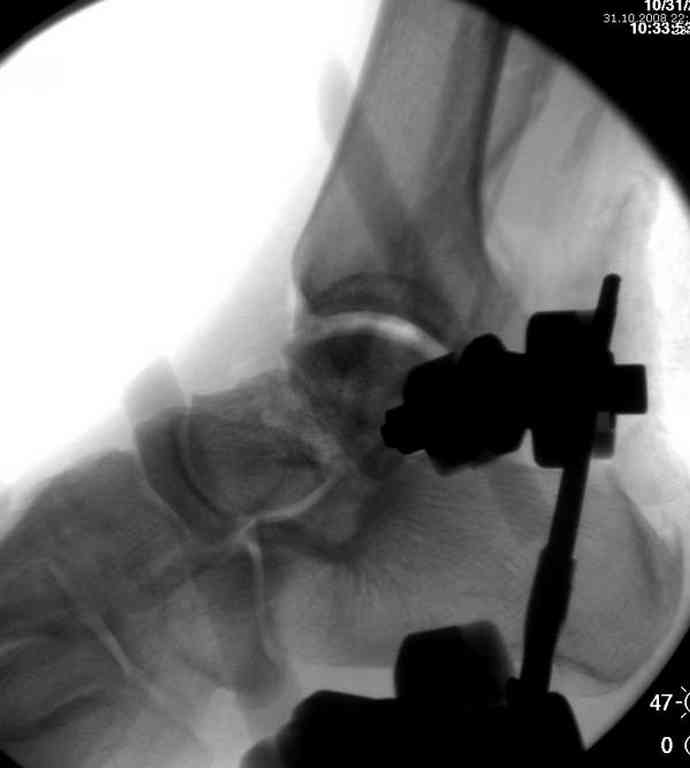

Здесь на фото примеры:

Переломовывих тарана с повреждением медиальной стороны. Через 4 часа после поступления проведена репозиция и фиксация тарана после Irrigation&Debridment. Частичное несращение медиальной лодыжки не беспокоит, вернулся к активному образу жизни. Полная нагрузка разрешена через 11 недель. Финальные снимки через 11 месяцев.

Второй случай прооперирован вчера.

10 дней назад поступил с открытым повреждением медиальной лодыжки и переломо вывихом таранной кости. Ургентно сделана репозиция с наложением наружного фиксатора + Irrigation&Debridment.

Во время репозиции выявили повреждение заднего сухожилия м. тибиалис и задней большеберцовой артерии. Медиальную рану удалось закрыть частично и установлен вакуум.

Дважды провели Irrigation&Debridment с заменой вакуума.

Вчера провели фиксацию.

Из-за многооскольчатости дистальной части малоберцовой, где невозможно было провести фиксацию шурупами, перелом зафиксирован подпирающей пластиной, которая должна служить дополнением отсутствующей дистальной части малоберцовой (lateral cortex substitute).

Для стабильности два шурупа на синдесмоз.

Медиальную рану с приближенными краями продолжаем вакуумировать (KCI). Наружный фиксатор оставлен на пару недель, надеюсь, небольшая рана будет гранулировать и закроется без кожной пластики. Фиксация медиальной ложыжки не планируется.